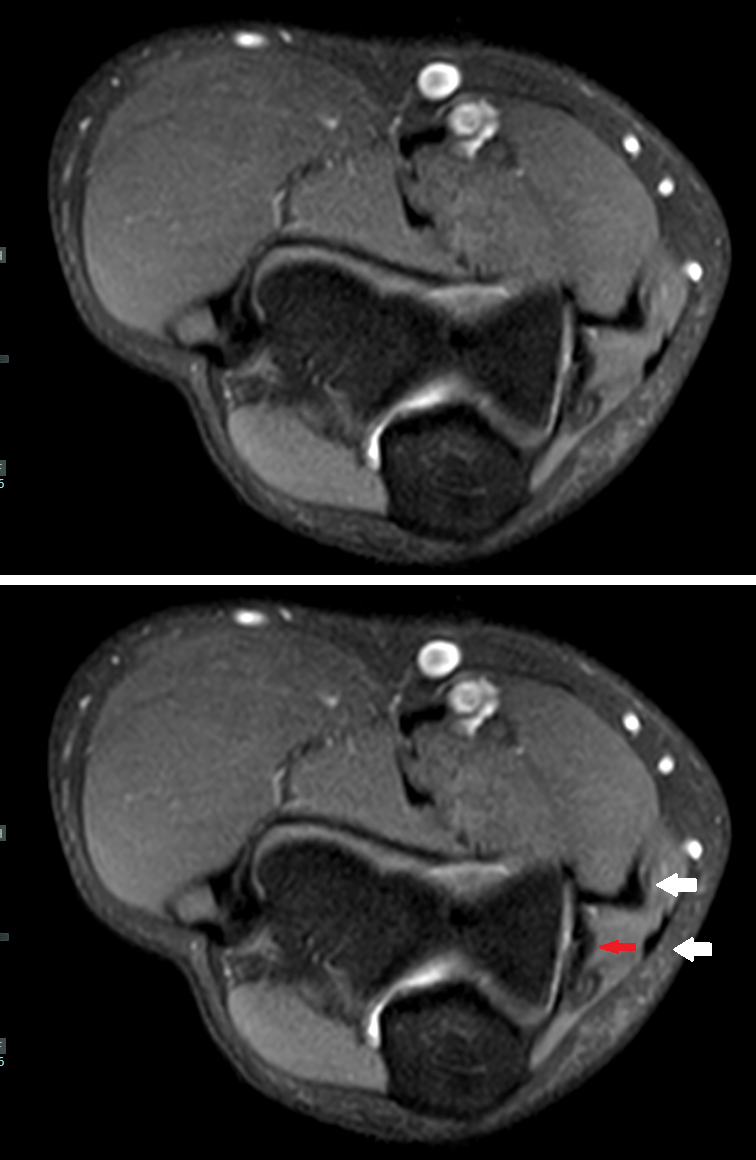

"Check out this little black line here," Misra says. "That's the ligament. That's the UCL. That's the one everybody cares about."

On the screen, my UCL appears as a sliver of black between other structures that appear in grays and whites.

A solid black band is good. It means the ligament is intact. It appears black because the MRI machine doesn't actually capture signals from ligaments or tendons; rather, it captures what is around them: soft tissue and fluid, which contain the water the MRI magnetizes.

So, a perfectly intact ligament is a bit of a paradox on an MRI: the absence of anything is a good thing.

If it's torn, or completely torn, there will be slices or patches of white cutting through or obscuring the ligament. Swelling around the ligament can make diagnosing an issue difficult.

"Sometimes it's not just the ligament itself that is swollen, it is everything outside of it," Misra says. "And then in terms of what we are looking for, it depends. If it's just sprained, instead of it being just a nice black line, maybe it will be thicker, so you cannot really tell where the margins are any more. Then there will be edema in it."

Misra adds: "Edema is water, so there will be higher, brighter signal with it. 'Oh look, it's thick and bright, but it's not torn. We're going to call it a sprain.'"